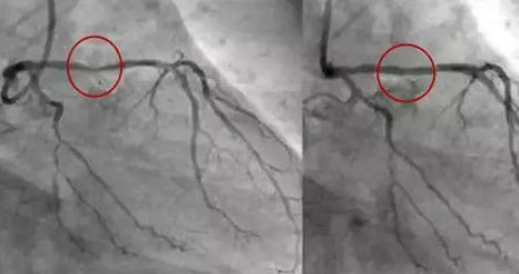

然后放入較細(xì)的導(dǎo)管,注入造影劑,通過X光透視,可以從電腦屏幕上知道血管的粗細(xì)和方向,確定最終的堵塞,安裝位置。

而解決冠狀動(dòng)脈的狹窄或閉塞的方法就是冠狀動(dòng)脈介入術(shù)(也叫心臟支架手術(shù))。